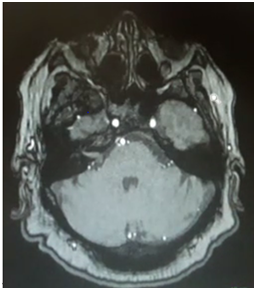

Gufoni repositioning maneuver was performed for BPPV of the right lateral canal (canalithiasis). She was asked to come back 72hours later and she then reported feeling better; Mc Clure maneuver was performed and the nystagmus still persisted with the same characteristics; Gufoni maneuver was performed for the second time and she was asked to come back again 72hours later, no changes were observed; a posterior fossa and cerebellum MRI was requested with contrast and angio-resonance where a Neuroma of the eighth cranial pair of the right ear and a frontal falxmeningioma were observed (Figure 1). Patient´s sign lasted few months, she was not operated. Patient’s sign lasted few months, she did not undergo surgery.

Figure 1 T1-weighted RMI with gadolinium where neuroma is observed at the right cerebellar angle.